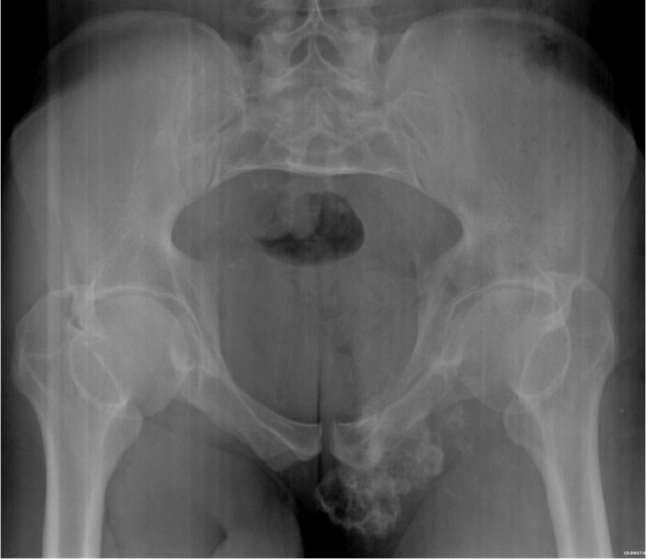

Figure 1. A fusiform, lucent defect with scalloping of the inner cortex and periosteal reaction is noted with extension into the soft tissue along with stippled calcification of the cartilage matrix.

Radiography

A large osteolytic, expansile lesion is noted in the left pubic bone with faint and characteristic popcorn calcification of cartilaginous matrix. There is also evidence of cartilaginous matrix mineralization, which is stippled, nodular, and showing rings and arcs.